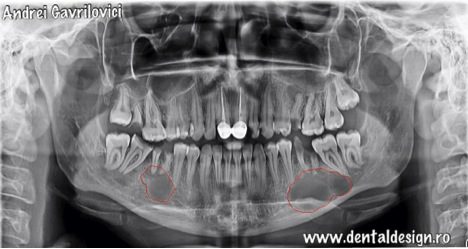

În acest articol vom prezenta intervenția chirurgicală pentru extirparea chistului aferent primului molar inferior de pe partea stângă. Dupa consultul chirurgical s-a decis efectuarea tratamentelor de canal la dinții care sunt prinși în formațiunea chistică, urmând ca porțiunea din rădăcină care este infectată să fie îndepărtată pentru a preveni contaminarea întregului dinte.

*Cu albastru este defectul osos ce ar fi ramas dacă se făcea extracția la timpul potrivit, iar cu roșu este defectul osos ce a rămas după îndepărtarea chistului, defect ce a trebuit umplut cu granule de os

Intervenția chirurgicală a durat aproximativ două ore, a fost necesar un lambou trapezoidal prin care s-a dat la o parte gingia de pe os din dreptul caninului până în dreptul ultimului molar pe partea stângă. După aceea s-a extras restul radicular care a cauzat infecția, s-a frezat din osul vestibular și s-a îndepărtat formațiunea chistica. Concomitent s-a realizat rezecția dinților ale căror rădăcini au fost prinse în chist și s-a realizat adiția osoasă și repoziționarea gingiei cu ajutorul firelor de sutură.

*rezectia apicală: porțiunea din rădăcina colorată în roșu a trebuit îndepărtată deoarece era prinsă în procesul infecțios